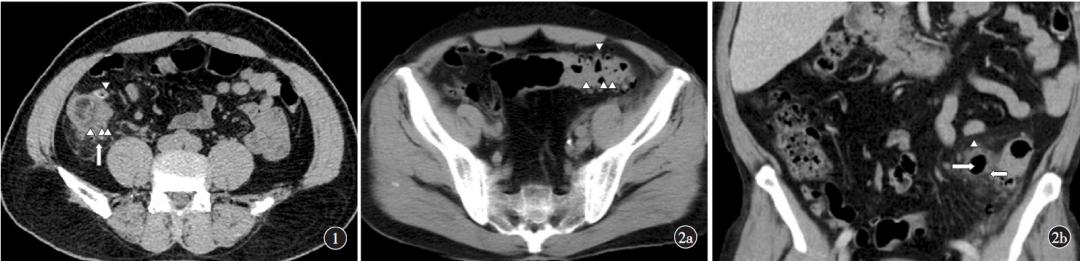

图①病例:患者,男性,50岁,CT轴位示回盲部多发憩室(三角箭),邻近肠壁增厚,憩室周围脂肪密度增高、筋膜增厚(长箭),手术病理证实为急性阑尾炎合并回盲部多发憩室炎。

图②病例:患者,男性,63岁。②a:CT轴位示乙状结肠多发憩室(三角箭);②b:CT冠状位重组示乙状结肠系膜侧憩室(三角箭),周围脂肪密度增高(长箭),憩室周围积气(短箭)。